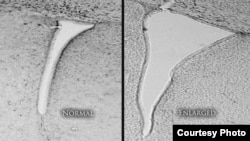

A mouse brain that was exposed to polluted air shows an enlarged lateral ventricle (right) compared with a mouse whose air was clean and filtered. Enlarged lateral ventricles are associated in humans with autism and schizophrenia. (University of Rochester

เมื่อทีมนักวิจัยทำการตรวจดูตัวสมองของหนูทดลองที่สูดอากาศที่มีมลพิษเข้าไป และพบว่าโพรงสมองข้าง ซึ่งเป็นส่วนหนึ่งของระบบโพรงสมองของสมอง มีขนาดใหญ่กว่าปกติ 2 ถึง 3 เท่าตัว ศาสตราจารย์ Cory-Slechta หัวหน้าทีมวิจัยกล่าวว่าในคนเรา โพรงสมองข้างที่มีขนาดใหญ่กว่าปกติ เกี่ยวข้องกับความบกพร่องทางความคิดแบบออติสซึ่ม โรคจิตเภท และความบกพร่องทางความคิดอ่านชนิดอื่นๆ

ศาสตราจารย์ Cory-Slechta กล่าวว่านี่เป็นตัวชี้ความผิดปกติทางการพัฒนาในสมอง เป็นตัวชี้ความบกพร่องทางการพัฒนาในเด็กด้านพฤติกรรม ระดับไอคิว ความสามารถในการคิดและการตรึกตรองอย่างลึกซึ้ง ซึ่งเป็นความบกพร่องที่จะคงอยู่ถาวร